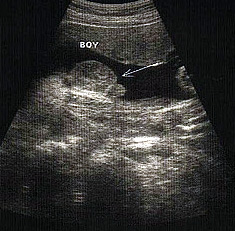

الولد

الأسبوع ال17